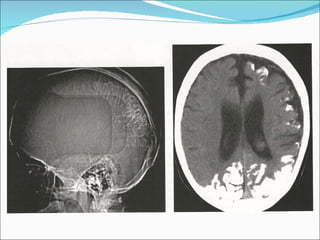

1) O documento descreve o Síndrome de Sturge-Weber, uma condição neurocutânea não hereditária caracterizada por nevo facial e convulsões. 2) O Angioma Cutâneo de Sturge-Weber aparece na área de inervação do trigêmeo, enquanto o Angioma Leptomeningeal aparece nos sulcos corticais parietais e occipitais. 3) Os achados de imagem incluem realce no espaço subaracnóideo e hipersinal na substância branca adjac